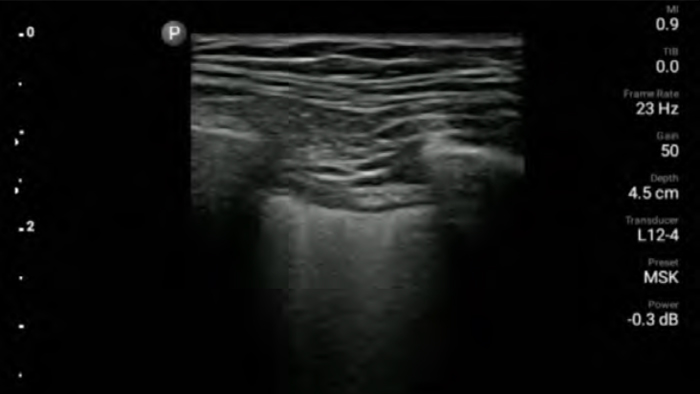

Ecograful portabil Lumify pentru anesteziologie vă ajută să vizualizaţi clar definiţia limitelor cu plasarea acului, nervii, vasele şi planurile fasciale din jur.

Lumify vă ajută să vizualizaţi clar plasarea acului, nervii, vasele şi planurile fasciale înconjurătoare.